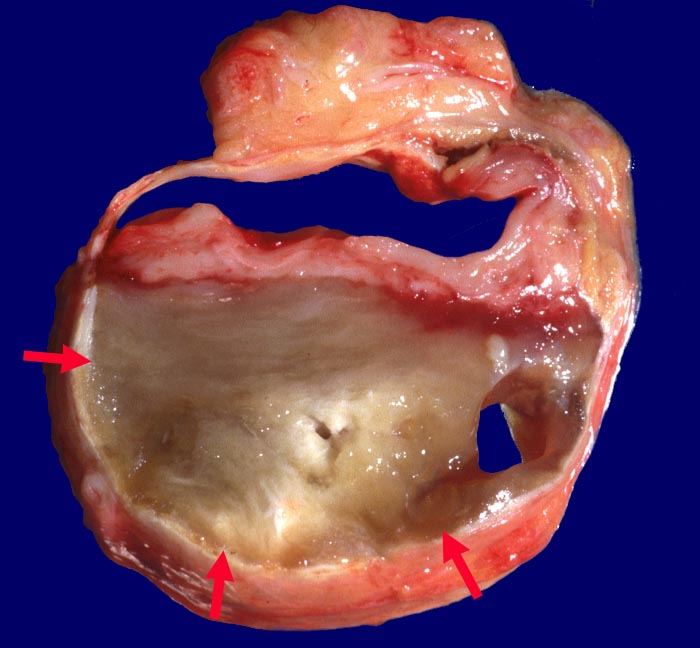

Subtotal thrombosiertes Aneurysma verum

Aorta abdominalis

Querschnitt durch das Aneurysma. Erweitertes Lumen (8cm Durchmesser) mit hyalinisierter ► Wandthrombose.